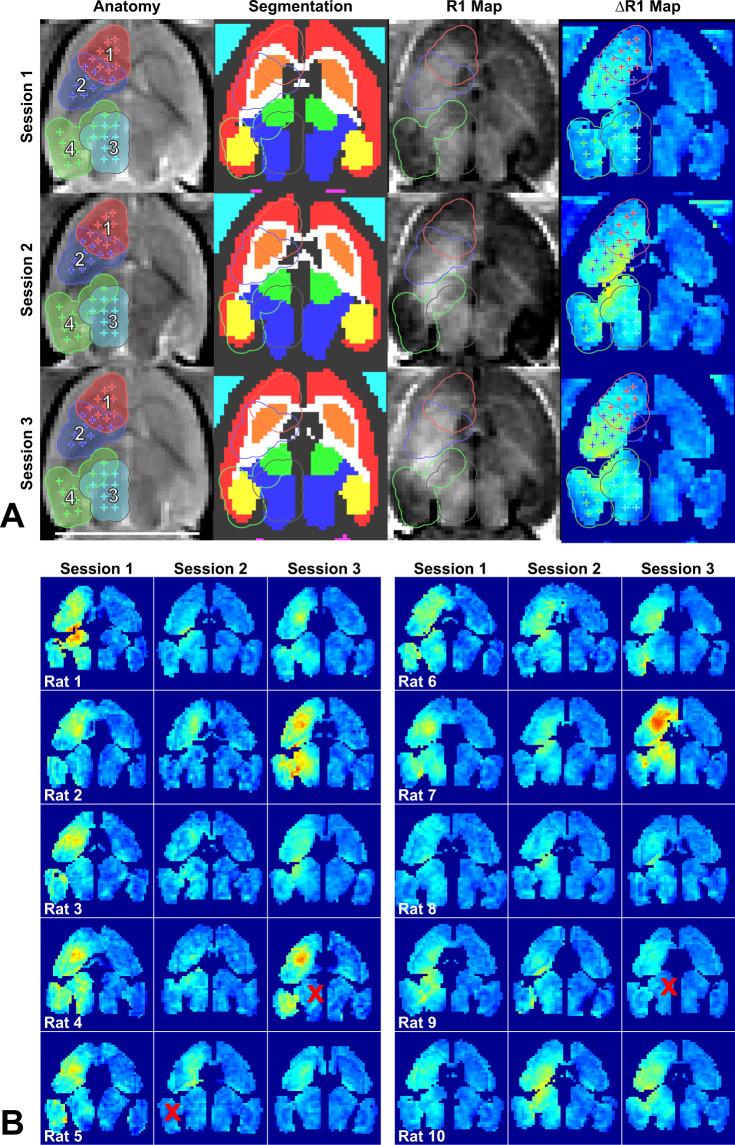

We investigated controlled blood-brain barrier (BBB) disruption using a low-frequency clinical transcranial MRI-guided focused ultrasound (TcMRgFUS) device and evaluated enhanced delivery of irinotecan chemotherapy to the brain and a rat glioma model. Animals received three weekly sessions of FUS, FUS and 10 mg/kg irinotecan, or irinotecan alone. In each session, four volumetric sonications targeted 36 locations in one hemisphere. With feedback control based on recordings of acoustic emissions, 98% of the sonication targets (1045/1071) reached a pre-defined level of acoustic emission, while the probability of wideband emission (a signature for inertial cavitation) was than 1%. BBB disruption, evaluated by mapping the R1 relaxation rate after administration of an MRI contrast agent, was significantly higher in the sonicated hemisphere (P < 0.01). Histological evaluation found minimal tissue effects. Irinotecan concentrations in the brain were significantly higher (P < 0.001) with BBB disruption, but SN-38 was only detected in <50% of the samples and only with an excessive irinotecan dose. Irinotecan with BBB disruption did not impede tumor growth or increase survival. Overall these results demonstrate safe and controlled BBB disruption with a low-frequency clinical TcMRgFUS device. While irinotecan delivery to the brain was not neurotoxic, it did not improve outcomes in the F98 glioma model.

我们使用低频临床经颅 MRI 引导聚焦超声(TcMRgFUS)设备研究了可控的血脑屏障(BBB)破坏,并评估了伊立替康化疗药物递送至大脑的效果和在大鼠脑胶质瘤模型中的效果。动物接受了每周三次的 FUS、FUS 和 10mg/kg 伊立替康或单独伊立替康治疗。在每次治疗中,四个容积式超声波靶向一个半球中的 36 个位置。通过基于声发射记录的反馈控制,98%的声发射目标(1045/1071)达到了预先定义的声发射水平,而宽带发射的概率(惯性空化的特征)大于 1%。通过给药 MRI 对比剂后测量 R1 弛豫率来评估 BBB 破坏,发现超声波治疗半球的 BBB 破坏明显更高(P<0.01)。组织学评估发现组织影响最小。BBB 破坏后,大脑中的伊立替康浓度显著升高(P<0.001),但仅在<50%的样本中检测到 SN-38,且仅在过量的伊立替康剂量下才检测到。伊立替康与 BBB 破坏并不会阻碍肿瘤生长或增加存活率。总的来说,这些结果表明低频临床 TcMRgFUS 设备可安全且可控地破坏 BBB。尽管伊立替康递送至大脑并未引起神经毒性,但它并未改善 F98 脑胶质瘤模型的结果。